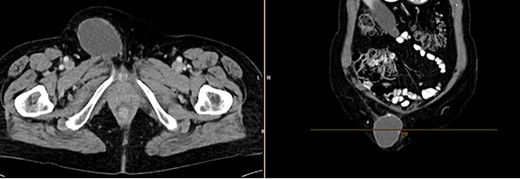

Further clarification was sought through a computed tomography (CT) scan of the entire abdomen (Fig. 1). The CT from 25 February 2022 showed an oval, encapsulated structure in the right groin area, most likely interpreted as a soft tissue hematoma. No active bleeding was observed. An enlarged lymph node was considered as a differential diagnosis. A follow-up CT on 1 August 2022 showed a size-progressive formation within the suspected right inguinal hernia compared with the previous examination in February (Fig. 2). There was no evidence of tumor recurrence or metastasis-suspect lesions intra-abdominally. A previous hysterectomy was also noted.

CT of the abdomen from 1 August 2022: size-progressive formation within the right inguinal hernia compared with the previous examination from 25 February 2022; no indication of tumor recurrence or metastasis-suspect lesions intra-abdominally, post-hysterectomy.